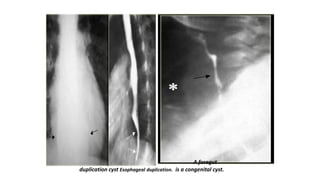

A foregut

duplication cyst Esophageal duplication. is a congenital cyst.